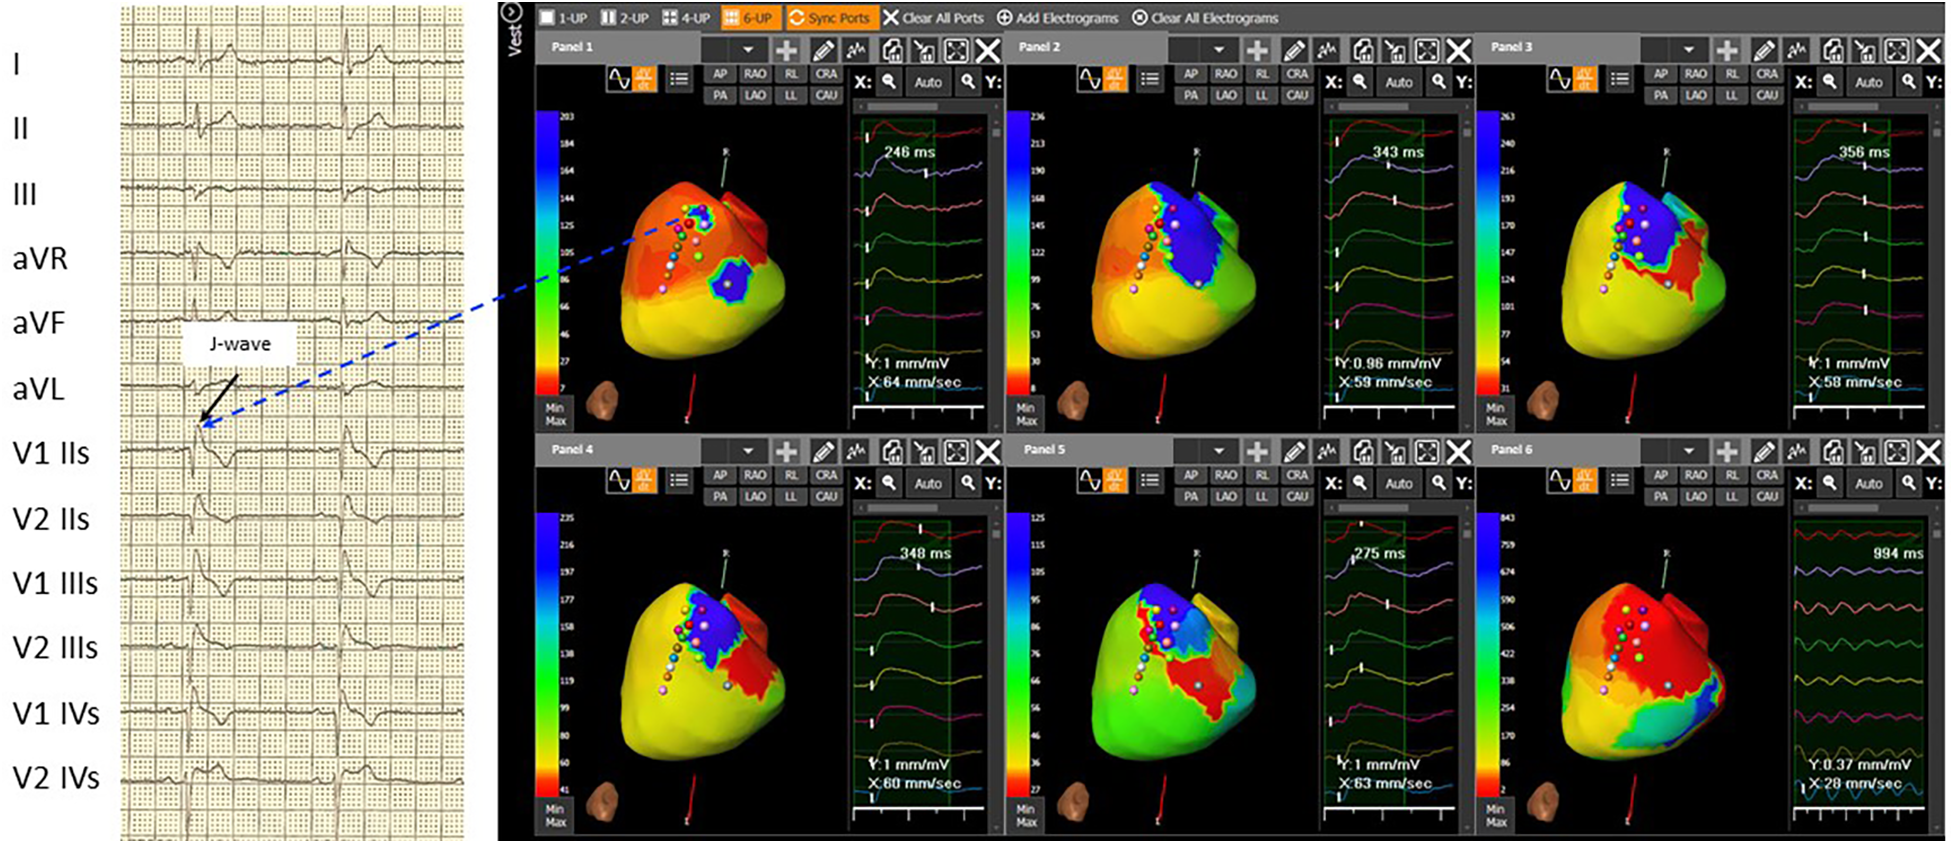

Figure 2

The 3D epicardial RVOT surface was performed with the support of a non-contact cardiac mapping system (CardioInsight) during ajmaline test. In basal conditions, the map shows not late RVOT but only small late areas (related to the presence of J-wave and right delay present on the basal ECG) (Panel 1). Panel 2, at 5 minutes after the ajmaline infusion, a delay appears on the RVOT in the antero-septal area. Panel 3, at 7 minutes after the ajmaline infusion, notice the maximum expression of the Brugada ECG pattern, extension of the delay in the entire anterior area of RVOT, and the appearance of functional block areas. A clear change in color between the later (blue area) and the earliest (red area) is observed in Panel 4: at 15 minutes after the ajmaline infusion, there is a reduction of the delayed zone in RVOT and persistence of the functional block area (green line). At 30 minutes after the ajmaline infusion, there is still a reduction of the late area in the RVOT and the disappearance (or clear reduction) of the block areas in Panel 5. The activation during induced ventricular fibrillation shown triggering zone (earliest) is depicted in Panel 6 that coincides with the most late in sinus rhythm in Panel 3. Note: ECG: IIs, second intercostal space; IIIs, third intercostal space; and IVs, fourth intercostal space.

After gaining informed consent, the novel ECG marker denoted “dST-Tiso interval” was assessed and appeared to be 340 ms (Figure 1, Panel B). In our previous study, we demonstrated that the interval between the onset of the coved ST-segment elevation and its return to the isoelectric line in leads V1 and V2 (dST-Tiso interval >300 ms) serves as a robust predictor of VA inducibility when observing the drug-induced BrS type-1 pattern (7). The patient underwent ajmaline test. Also, a T-wave alternans due to alternating activation during ajmaline infusion at 7 min was documented (Figure 1, Panel C). The T-wave morphology in the patient with BrS, exhibiting multiple ajmaline-induced electrogram fluctuations, reveals a notable reliance on the strength of epicardial activation. According to the value of dST-Tiso interval, in order to assess the severity of the substrate, we decided to perform a programmed electrical stimulation (PES) and to study the activation maps using non-invasive ECGi. The 3D epicardial RVOT surface was performed with the support of a non-contact cardiac mapping system (CardioInsight). During the ajmaline test, activation maps were performed in sinus rhythm, under baseline condition (preajmaline infusion), during ajmaline infusion (1 mg/kg in 5 min), and during PES according to the protocols described by Brugada et al. and Priori et al. (11, 12). These protocols consisted of two drive cycles (600 and 400 ms, S1) and three extrastimuli (S2–S4). A minimum coupling interval of 200 ms was established for premature beats in the case of S2 and S3, and it was set to a refractoriness period for S4. During the PES, a VF was induced. At baseline, there were “no areas” exhibiting abnormal EGM readings on the anterior part of the epicardium in the RVOT. However, during ajmaline infusion, a BrS type-1 pattern became evident, and an area of slow activation developed along the anterior wall of the epicardial RVOT. The examination of the propagation map unveiled the presence of several instances of conduction block in this pathological epicardial region, indicating interruptions in electrical conduction. These conduction blockages were observed both in the central part and in close proximity to the border zone between the normal and slow conduction areas (Figure 2, Panels 1–6). Following that, we examined the baseline maps to compare the direction of conduction. It was observed that the line of conduction block that emerged after ajmaline infusion was not present in the baseline maps. It is interesting to observe the comparison between the activation map in the progress of ventricular fibrillation (VF) (Supplementary Video, Panel A) compared with the activation map at 7 min from the ajmaline infusion (Supplementary Video, Panel B). By observation, the 7-min propagation in sinus rhythm confirms the block areas and coincides with an “aborted” reentry mechanism (i.e., with block in entry and exit). In the case of the triggering of VF with three extrastimuli from RVOT, the antegrade activation front finds the same block area followed by a late activation with a reentry mechanism that leads to the VF triggering. Ultimately, a genetic test was required to identify the genetic alteration consistent with BrS, and subsequently, the patient successfully underwent transvenous single-chamber defibrillator implantation (SC-ICD). At the 6-month follow-up, the patient was asymptomatic, and infrequent ventricular extrasystole and non-sustained ventricular tachycardia (maximum three beats) were recorded.